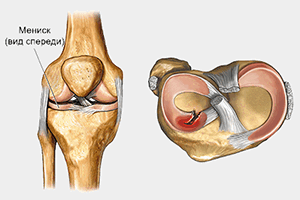

Мениски - это особые прослойки, располагающиеся внутри коленного сустава и состоящие из фиброволокнистого хряща полулунной формы. Мениски сглаживают несоответствие круглых мыщелков бедренной кости и плоской большеберцовой кости, выполняют амортизирующую и стабилизирующую функции.

Всего в коленном суставе два мениска: внутренний (медиальный) и наружный (латеральный).

Мениски в поперечном разрезе имеют треугольную форму. “Основание” мениска крепится к капсуле сустава. В этом месте в толщу мениска проникают питающие его кровеносные сосуды. Врачи травматологи-ортопеды называют эту часть мениска красной зонной. В центре мениска сосуды ветвятся, превращаются в капилляры – это так называемая розовая зона. Вершина треугольника направлена в полость сустава, она лишена кровоснабжения и считается белой зоной.

Рис. 3. Поперечное строение мениска 1. Красная зона 2. Розовая зона 3. Белая зона

Такое деление при повреждениях менисков позволяет принимать решение о том или ином виде лечения.

Рис. 4. Варианты повреждения менисков.